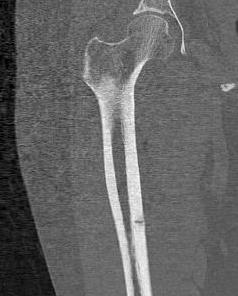

Fractures

Transverse fractures

- begin laterally

- minimal comminution

- incomplete versus complete

Incomplete femoral shaft AFF / dreaded black line

Femoral stress fracturecomplete AFF

Complete AFF